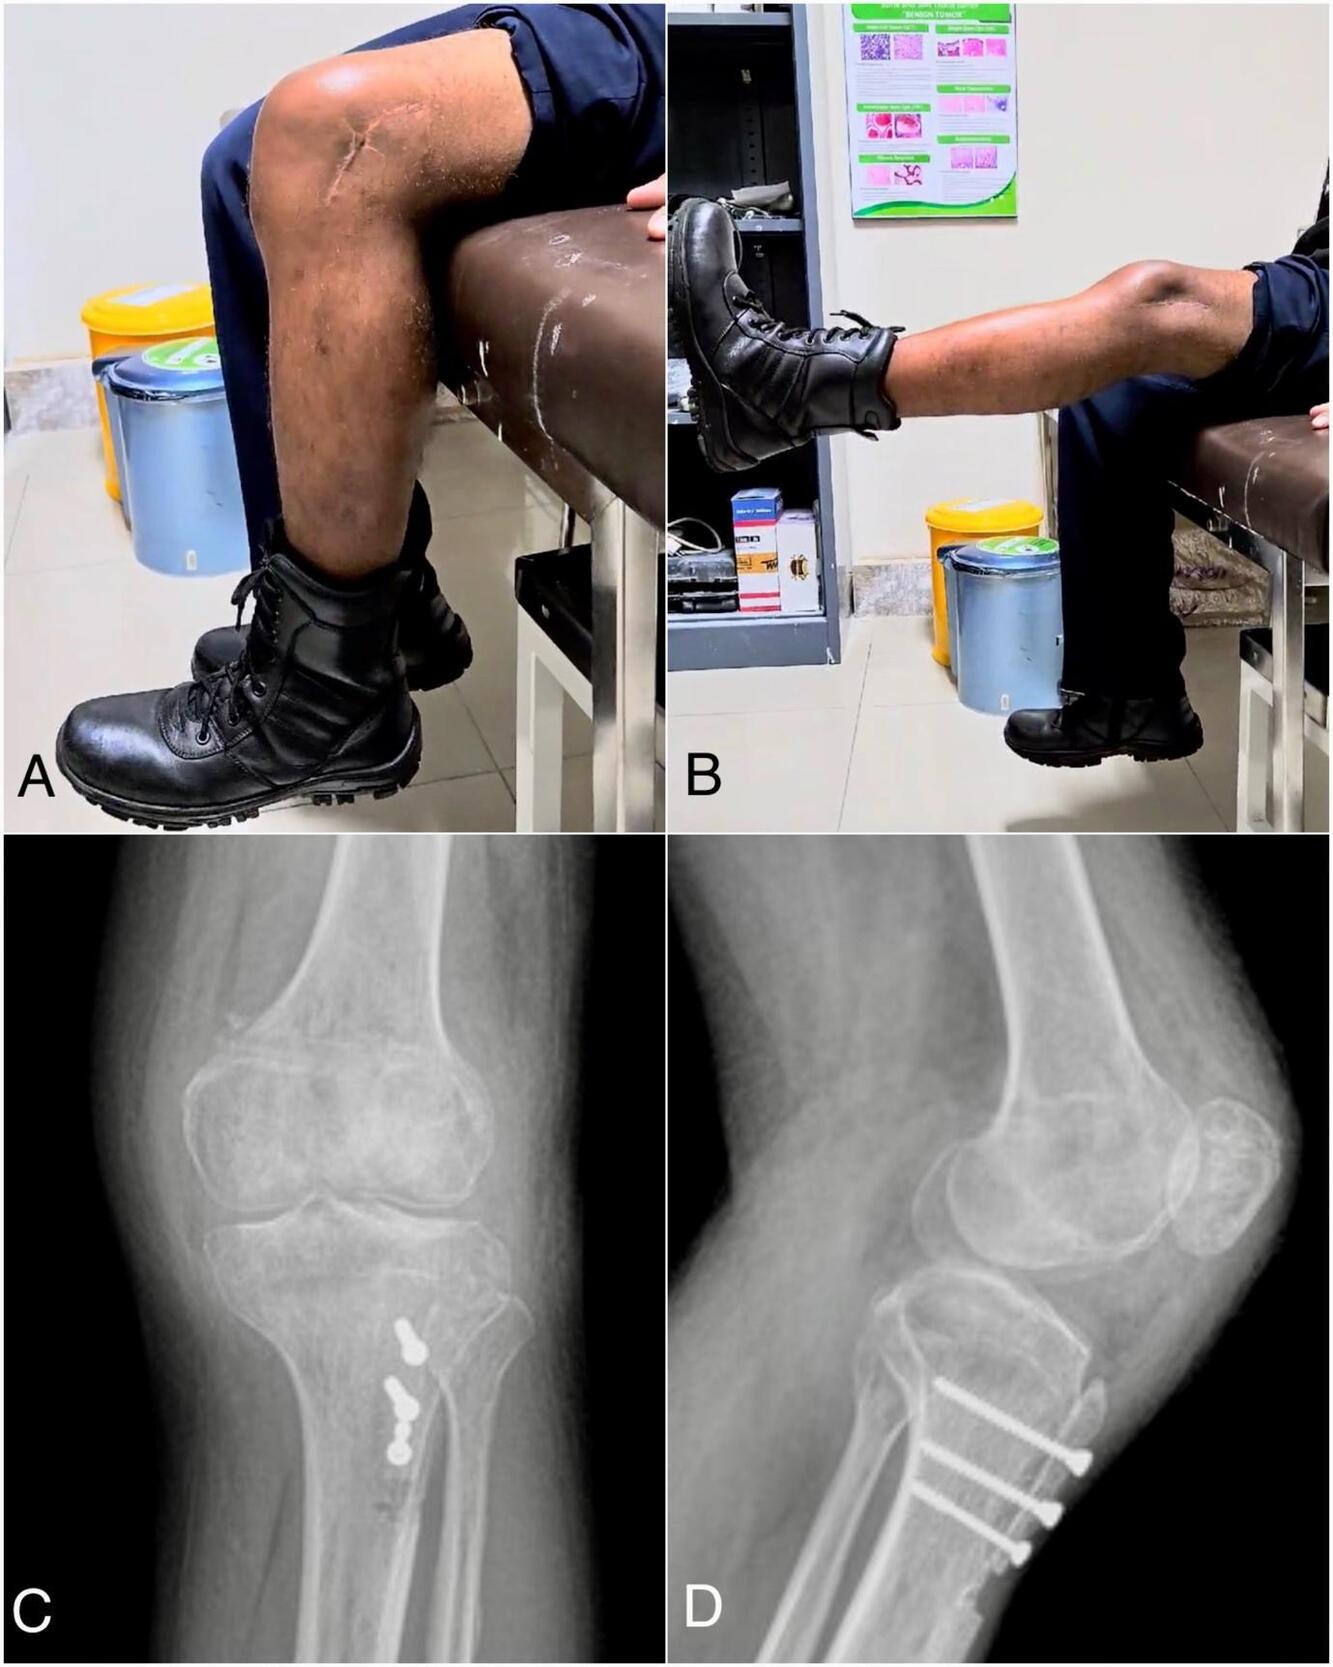

The physical examination showed a deformity of the left knee, and a J-track sign was visualized on his lateral side of the left knee (Fig 1A, 1B). The apprehension test showed a positive sign of lateral dislocation of the patella but without pain. The passive lateral patellar tilt test yielded a negative result due to the widespread stiffness and tightness of the soft tissue connection along the lateral border of the patella. There was no swelling, but the patella was clearly palpable on the lateral knee. Only 75 degrees of knee flexion range of motion and 20 degrees of knee extension range of motion from the horizontal axis. Clinical scoring using the Tegner Lysholm score of 69 and the IKDC score of 62.1, which indicating moderate functional limitation. Anteroposterior and lateral knee radiographs, as well as coronal and axial MRI scans, revealed a patellar lateral dislocation associated with trochlear dysplasia (Fig 1).

Follow-up conducted at six months and twenty months. The patient’s anterior based patellar position well-maintained. The physical examination indicated a flexion range of 100 degrees improve into 115 degrees and an extension maintain range of 0 degrees from the horizontal axis (Fig 4). Evaluation with clinical scoring showed an improvement, as indicated by the Tegner Lysholm score of 85 and the IKDC score of 80.5 (Table 1). Patient was satisfied with the results and able to go back to his regular activities with no recurrence dislocations.